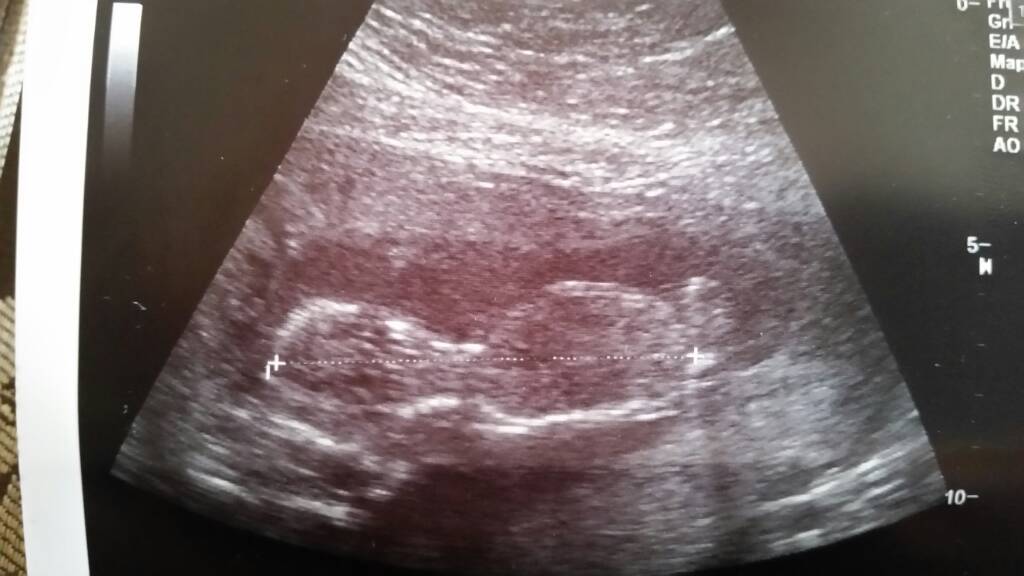

Każdy waży juz 100 gram, dacie wiarę? [emoji38]